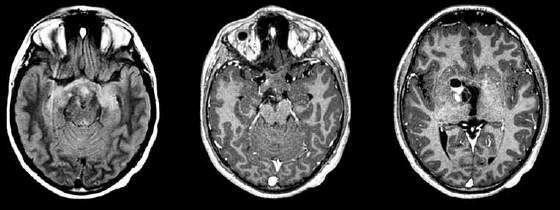

Paciente com atraso global do desenvolvimento e epilepsia. Na investigação foi realizada a ressonância magnética de crânio a seguir.

Enunciado 4100247-1

A achado de imagem sugere